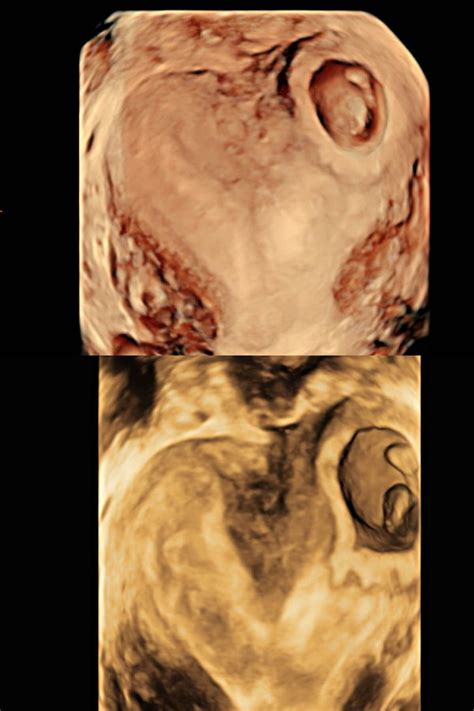

Diagnosing a Bicornuate Uterus

Diagnosing a bicornuate uterus often occurs during routine prenatal care or when investigating the cause of recurrent pregnancy loss. Several diagnostic methods can be employed:

• Ultrasound: Transvaginal ultrasound is commonly used to visualize the uterus and detect any abnormalities in its shape.